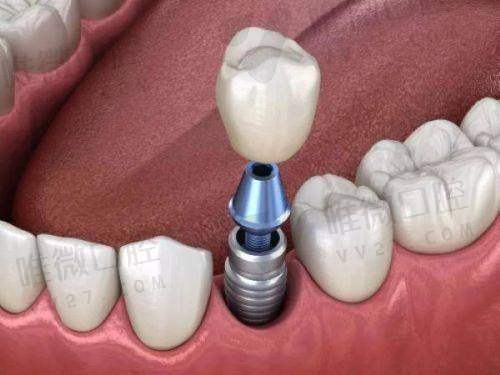

作为连锁医美品牌,宁波美莱不仅在皮肤抗衰领域拔得头筹,口腔中 心在种植牙技术方面也非常专精。他们采用德国和瑞士等高端种植体品牌,如费亚丹、iti和诺贝尔,手术主要以微创种植为主,还配备CBCT精细数据分析系统,上岗医生如李斌与张玉涛在局部种牙方面经验多。价格方面也意外地亲民,例如韩系登腾种植牙仅4500元起,适合预算型人群。

牙博士在宁波有多个院区,几乎覆盖了每个大型住宅密集区,医院配备3D导板微创种植技术,医生团队中像王道军、牟宗起均是高难种牙领域的佼佼者。这里较大优势是技术齐全,从穿颧穿翼、即刻负重到All-on-4半全口修复都能驾轻就熟,同时价格也较为亲民,让一些牙槽骨条件欠佳的客户也能负担得起。

恒美口腔以“专精+平价”路线打出市场,擅长在即拔即种和即刻负重种植上做深耕,减少患者等待时间,同时也提高了心理接受度。种植系统以国产与进口并重,适合预算紧张又想体验便利服务的人群。日常还有语音导航问诊系统,预约流程也相当效率高。

走亲民路线的牙壹家口腔,专攻中老年客户群,适合牙齿缺失较多者,如半口/全口缺牙。主打性价比,3880元起种植一颗韩国种植体含烤瓷冠,价格优势显著。周建国医生是老年种植领域的有名主诊,善于制定多次种牙计划,让牙缺失多年的顾客也安心修复。

主打数字化导航种植技术,是拥有较强技术背景的私立机构。该院对All-on-4/6全口种牙较为熟练,相关医生多为国有医院出身,如一些三等甲院校退役医生,方案制定严谨。硬核科技加传统经验,是这家医院较大优势。

牙贝恩专注处理复杂病例,例如骨量少、骨萎缩或美学前牙修复等。医生团队出自国内外高等医 科背景,合作的种植系统多为高端如诺贝尔、astra等。医院本身环境温馨,术后服务完善,适合讲求品质和术后长期使用成效的客户。

恩吉口腔是技术流派代表,引进了前列的4D导航系统,使种植牙更加精细无创。医生往往在术前进行多角度影像判断,制定更合适的个性化方案。该院还注重口腔健康普及和儿童牙科服务,种植牙价格层次丰富,用户满意度高。

佳兴通过CBCT和全景数字系统辅助种植,擅长处理高龄不适合手术类型的个案,并支持延迟种植、一次性种植、即刻修复等多种方法选择。医生团队拥有临床实操经验,非常注重术后咬合调节和美观度保持。